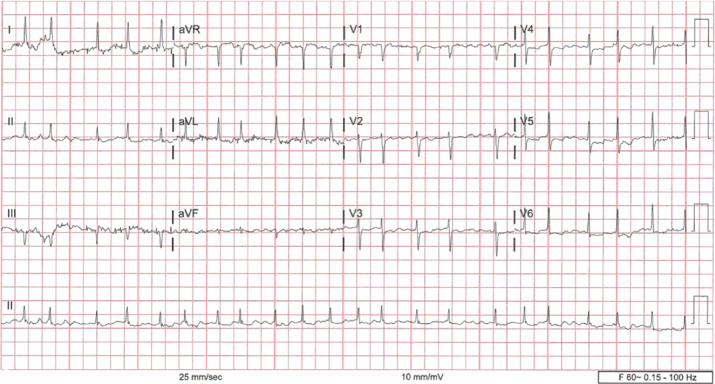

Digoxin, a cardiac glycoside and sodium-potassium adenosine triphosphatase inhibitor, has a narrow therapeutic index and is primarily prescribed for conditions such as systolic heart failure and atrial fibrillation. This narrow window increases the risk of toxicity, especially among susceptible populations. Although digoxin use has declined in recent decades and cases of toxicity have become less frequent, clinicians must remain vigilant, particularly with geriatric patients, who are more susceptible due to polypharmacy and reduced renal function. Here, we present a case of a 77-year-old woman with dementia who exhibited elevated digoxin levels and was successfully treated with digoxin immune Fab. While the use of immune Fab in chronic toxicity cases remains uncertain, our retrospective review of similar cases, managed both with and without immune Fab, provides insights into its role and limitations. We further underscore the importance of regular digoxin monitoring rather than checking the levels only during toxic episodes, as consistent monitoring can prevent fatal cases and reduce overall mortality.